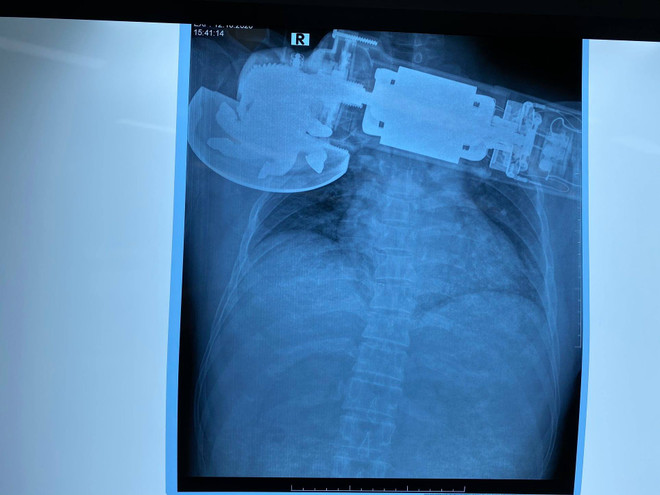

Cấp cứu một người đàn ông bị máy cắt găm sâu vào ngực phải ảnh 1Hình ảnh chụp X-Quang chiếc máy găm vào ngực của bệnh nhân. (Ảnh: PV/Vietnam+)

Sau khi khám, các bác sỹ thấy máy chà găm sâu vào thành ngực phải của bệnh nhân, sát bờ dưới xương, bờ mép vết thương nham nhở, phần mềm thành ngực bị cuốn vào trong máy chà gây khuyết hổng phần mềm, mất da và bầm dập da quanh tổn thương.

Bác sỹ Lê Hải Sơn-Phó Chủ nhiệm khoa Ngoại lồng ngực, người trực tiếp tiến hành phẫu thuật cho biết bệnh nhân bị bong lóc phần mềm, mất da và bầm dập da rất lớn ở vùng ngực bên phải. Các bác sỹ đã đánh giá tổn thương mạch máu, tình trạng của khoang màng phổi, rất may bệnh nhân này chưa có tổn thương đó.